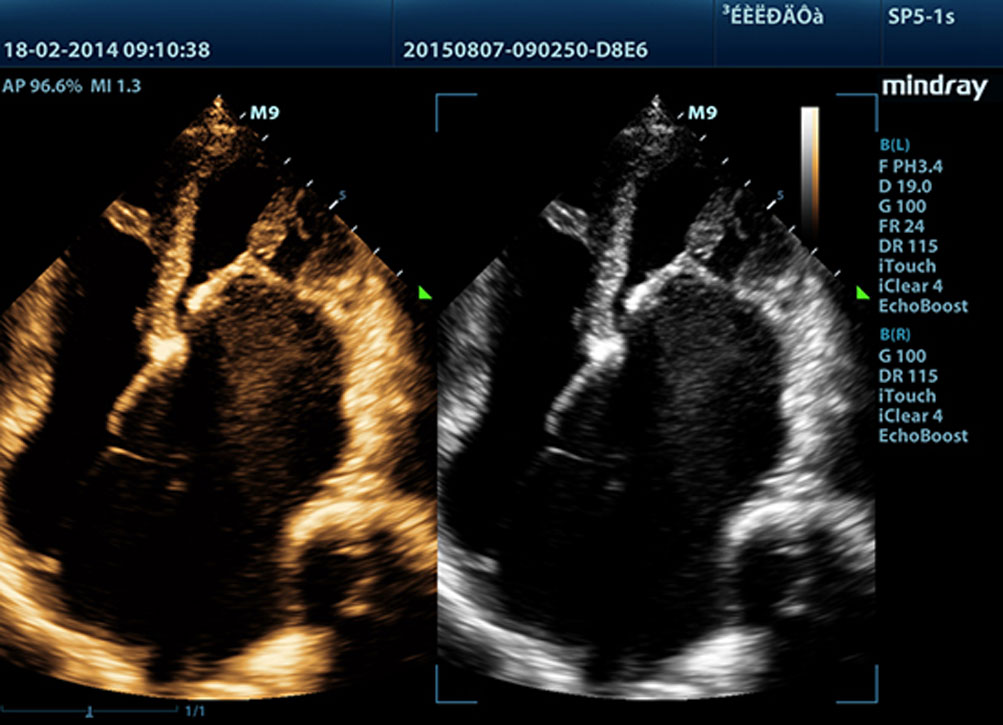

M9? ?????? ??? ??? ???? mQuadro? ???? ??? ??? ??? ??? ???? ???????. ??? ?? ??? ????? ???? ???? ?? ?? ?? ??? ?????. ???? ????? ??? ?? ?? ???, ?? ?? ???? ???? ????? ??? ?? ???????.

M9? ???? ?? ???? ?? ??? ??? ?????? ?????? ???? 3T ????? ??? ??? ????. ??? ??? ??? M9? ?? ??? ?? ?? ?? ? ?? ?? ???? ?? ???? ??? ?????.

Echo Boost?

??? ?? ??? ?????? ??? ??? ?? ???? ??? ??? ?? ? ?? ??? ???? ?? ?? ??? ?????? ?? ??? ????? ???? ?? ?? ?? ?? ??? ?? ?? ?? ??? ???? ?????.